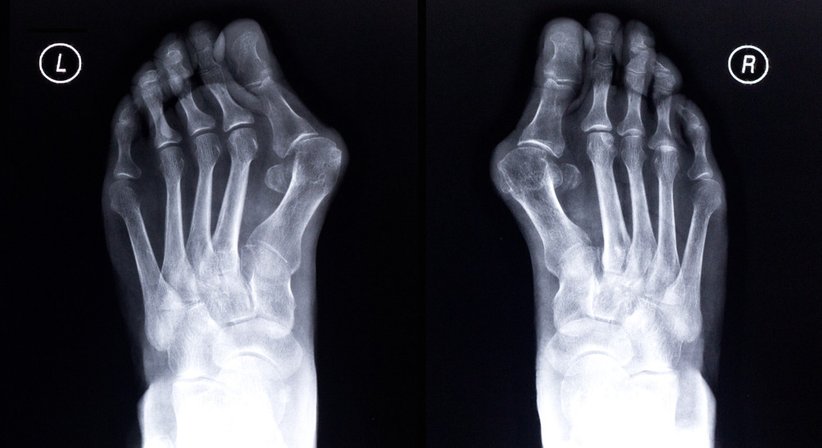

Schmerzen im Fuß sind so vielfältig wie ihre Ursachen. Spreizfuß, Senkfuß, Fersensporn, Hallux valgus,…aber auch Fehlstellungen, Überbelastung oder Verletzungen können Beschwerden in diesem Bereich auslösen. Wenn konservative Maßnahmen allein die Fußschmerzen unserer Patienten nicht lindern, kommt die Fußchirurgie zum Einsatz, und ich führe operative Eingriffe nach meiner Spezialisierung auf minimal-invasive Methoden durch.

Beim Hallux valgus etwa arbeite ich mit einer Technik, die auf herkömmliche Metallimplantate verzichtet und stattdessen bioresorbierbare Schrauben verwendet. Diese lösen sich nach zwölf bis 18 Monaten selbst auf, eine zweite Operation ist also nicht mehr nötig. Außerdem kann es zu keinen Unverträglichkeitsreaktionen auf Metalle kommen, und nach drei bis vier Wochen ist das Tragen von normalem Schuhwerk problemlos wieder möglich.